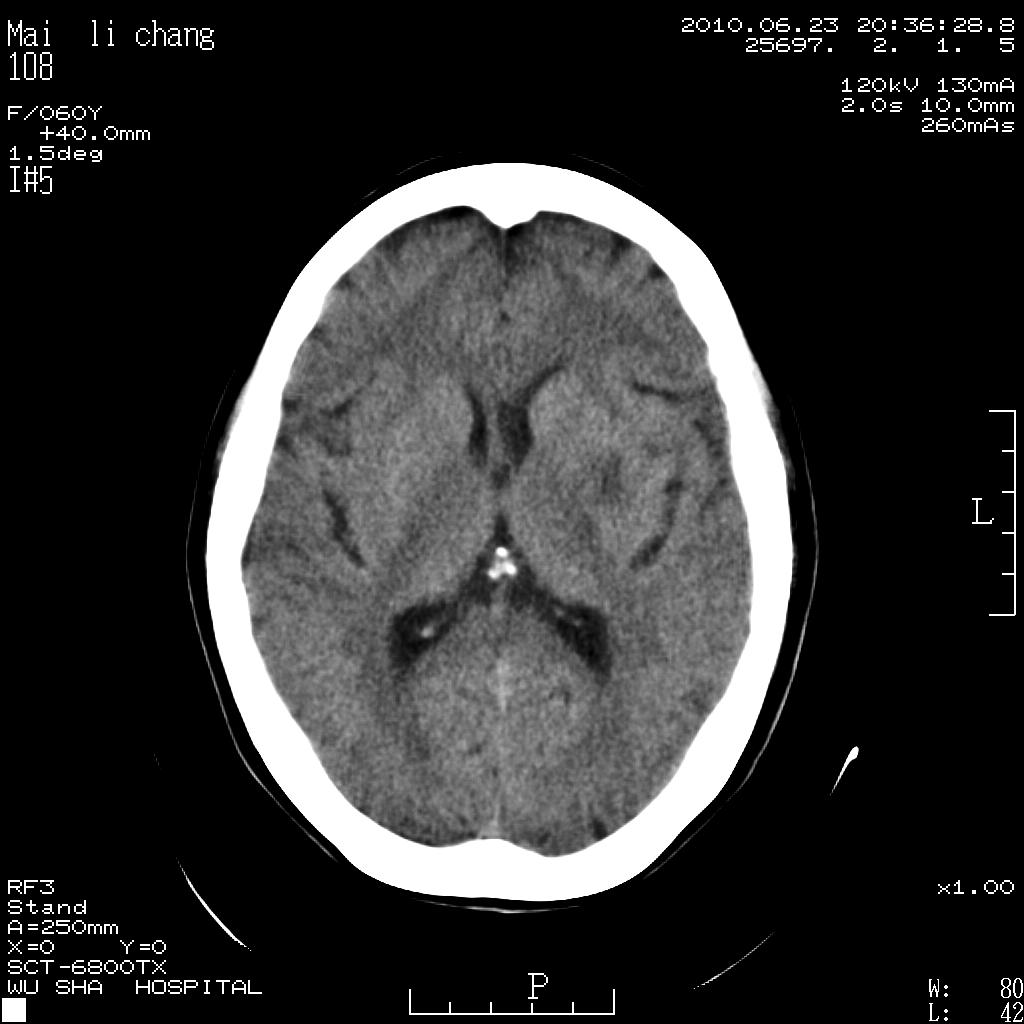

女性,60岁,右手无力一天

脑梗塞?并皮层下动脉硬化性脑病?还需要考虑什么?请大家指导,先谢了。

考虑左侧基底节区脑梗塞。

左侧基底节区及放射冠区多发脑梗塞。

左侧基底节区及侧脑室旁多发脑梗塞

2.左侧基底节区可见片状低密度病灶。

意见考虑脑梗塞。

左侧基底节区大面积梗塞,必要增强扫描协诊